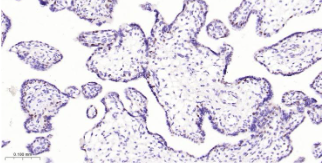

Immunohistochemical analysis of paraffin embedded Human placenta tissue slide using IHC0552H (Human Dnmt1 Kit).

12 Control slide (Human placenta) 1 slide RTU RT